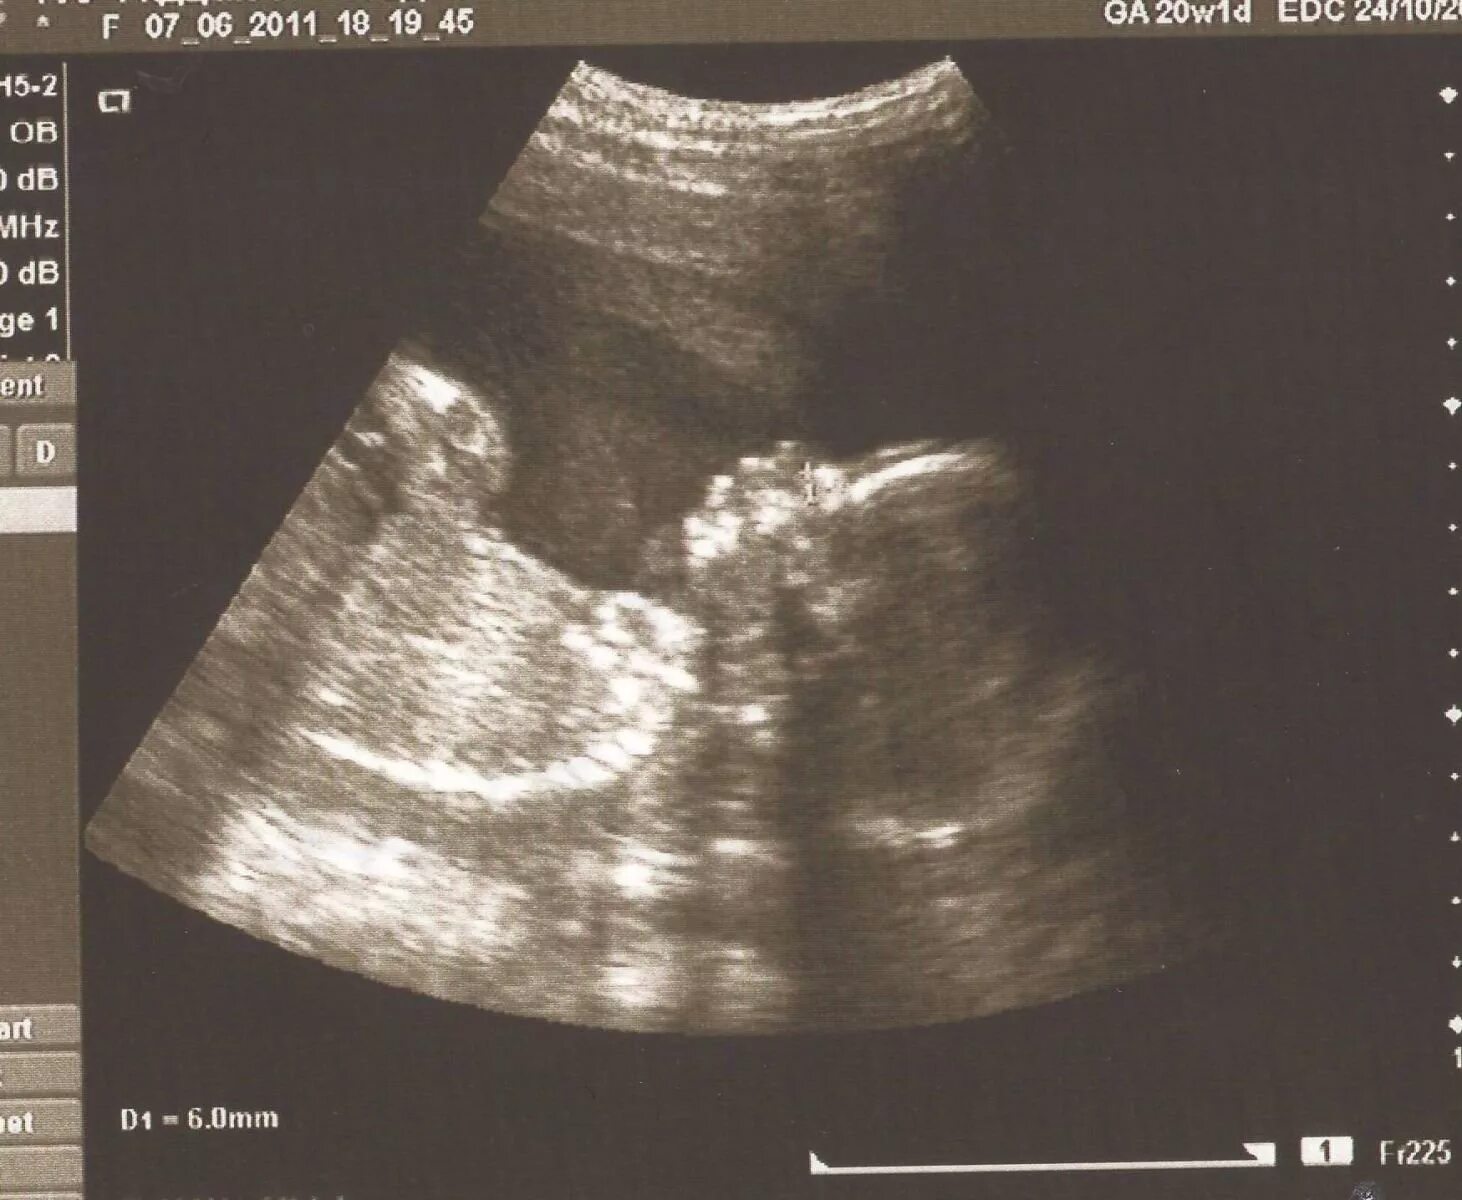

Через 20 недель